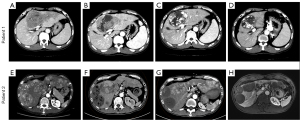

Treatment response

The objective response rate (ORR) and disease control rate (DCR) were comparable between groups, with the Dona-TACE group demonstrating 55.10% (95% CI: 40.23–69.33) and 75.51% (95% CI: 61.13–86.66) vs. 61.36% (95% CI: 45.49–75.64) and 81.82% (95% CI: 67.29–91.81) in the LEN-TACE group (P=0.541 for ORR; P=0.460 for DCR) (Table 2). Typical CT/MR images of the Dona-TACE group are shown in Figure 4.